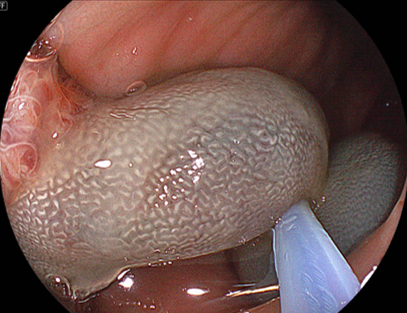

S状結腸の30mmの大型隆起性病変

LCIモードにおける弱拡大観察画像

先ほどの反対側の観察では、不整な微細表面構造が

認められます。よって術前診断では高異型度腺腫

(こういけいどせんしゅ)~粘膜内癌(ねんまくないがん)

を想定しました。